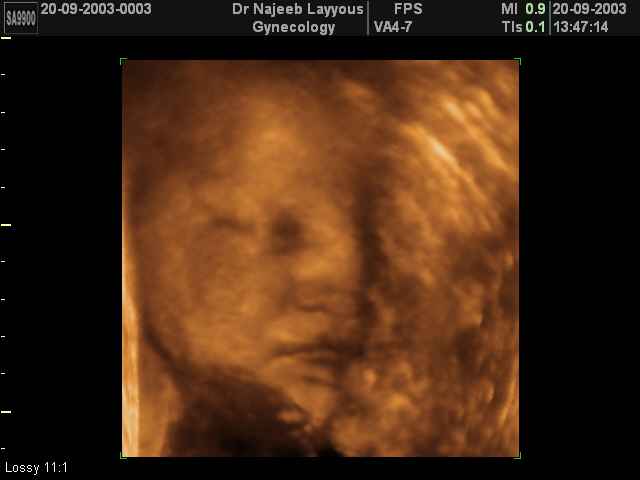

3D Fetal Face Ultrasound Scan Photos